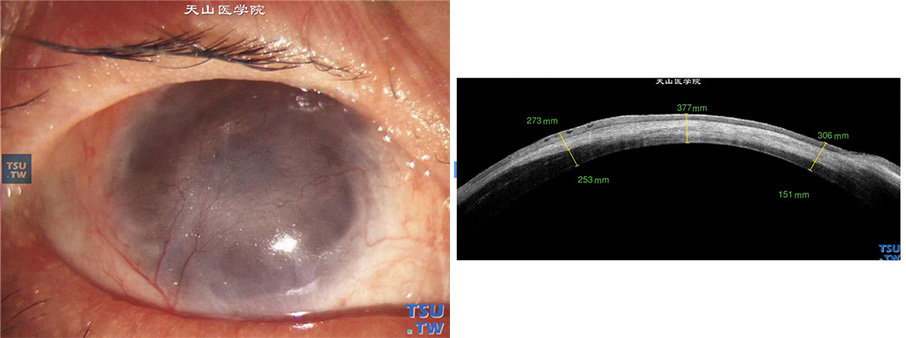

患者右眼,曾行羊膜移植术,3年前做过颌下腺移植和3次板层角膜移植术,病情暂时稳定,角膜植片浑浊,新生血管长入植片;角膜变薄,薄厚不均,角膜上皮下细小水泡,角膜植床影像较角膜植片致密,可以判定植床和植片的界限